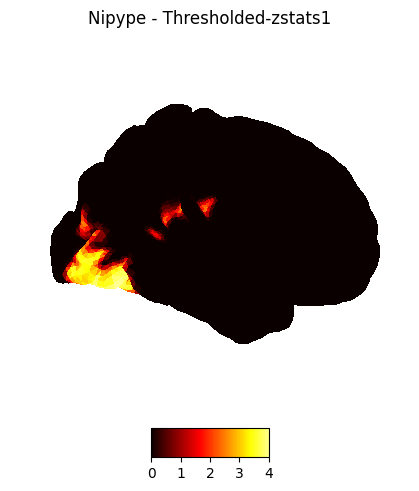

18

['/home/jovyan/workspace/books/examples/functional_imaging/output_level1/level1_results/01/reg_copes/_subject_id_01/_warpfunc0/cope4_flirt.nii.gz', '/home/jovyan/workspace/books/examples/functional_imaging/output_level1/level1_results/01/reg_copes/_subject_id_01/_warpfunc1/cope4_flirt.nii.gz', '/home/jovyan/workspace/books/examples/functional_imaging/output_level1/level1_results/02/reg_copes/_subject_id_02/_warpfunc0/cope4_flirt.nii.gz', '/home/jovyan/workspace/books/examples/functional_imaging/output_level1/level1_results/02/reg_copes/_subject_id_02/_warpfunc1/cope4_flirt.nii.gz', '/home/jovyan/workspace/books/examples/functional_imaging/output_level1/level1_results/03/reg_copes/_subject_id_03/_warpfunc0/cope4_flirt.nii.gz', '/home/jovyan/workspace/books/examples/functional_imaging/output_level1/level1_results/03/reg_copes/_subject_id_03/_warpfunc1/cope4_flirt.nii.gz', '/home/jovyan/workspace/books/examples/functional_imaging/output_level1/level1_results/04/reg_copes/_subject_id_04/_warpfunc0/cope4_flirt.nii.gz', '/home/jovyan/workspace/books/examples/functional_imaging/output_level1/level1_results/04/reg_copes/_subject_id_04/_warpfunc1/cope4_flirt.nii.gz', '/home/jovyan/workspace/books/examples/functional_imaging/output_level1/level1_results/05/reg_copes/_subject_id_05/_warpfunc0/cope4_flirt.nii.gz', '/home/jovyan/workspace/books/examples/functional_imaging/output_level1/level1_results/05/reg_copes/_subject_id_05/_warpfunc1/cope4_flirt.nii.gz', '/home/jovyan/workspace/books/examples/functional_imaging/output_level1/level1_results/06/reg_copes/_subject_id_06/_warpfunc0/cope4_flirt.nii.gz', '/home/jovyan/workspace/books/examples/functional_imaging/output_level1/level1_results/06/reg_copes/_subject_id_06/_warpfunc1/cope4_flirt.nii.gz', '/home/jovyan/workspace/books/examples/functional_imaging/output_level1/level1_results/07/reg_copes/_subject_id_07/_warpfunc0/cope4_flirt.nii.gz', '/home/jovyan/workspace/books/examples/functional_imaging/output_level1/level1_results/07/reg_copes/_subject_id_07/_warpfunc1/cope4_flirt.nii.gz', '/home/jovyan/workspace/books/examples/functional_imaging/output_level1/level1_results/08/reg_copes/_subject_id_08/_warpfunc0/cope4_flirt.nii.gz', '/home/jovyan/workspace/books/examples/functional_imaging/output_level1/level1_results/08/reg_copes/_subject_id_08/_warpfunc1/cope4_flirt.nii.gz', '/home/jovyan/workspace/books/examples/functional_imaging/output_level1/level1_results/09/reg_copes/_subject_id_09/_warpfunc0/cope4_flirt.nii.gz', '/home/jovyan/workspace/books/examples/functional_imaging/output_level1/level1_results/09/reg_copes/_subject_id_09/_warpfunc1/cope4_flirt.nii.gz']

<networkx.classes.digraph.DiGraph at 0x7f15fb955ba0>

The second-level GLM#

Here we choose the four copes from subject-01

Regapply#

This happens before the second-level GLM, all results from the first level are needed to be registered into the standard space

nipype_cope1 = './output_level1/level1_results/01/reg_copes/_subject_id_01/_warpfunc1/cope1_flirt.nii.gz'

nipype_cope2 = './output_level1/level1_results/01/reg_copes/_subject_id_01/_warpfunc1/cope2_flirt.nii.gz'

nipype_cope3 = './output_level1/level1_results/01/reg_copes/_subject_id_01/_warpfunc1/cope3_flirt.nii.gz'

nipype_cope4 = './output_level1/level1_results/01/reg_copes/_subject_id_01/_warpfunc1/cope4_flirt.nii.gz'

plotting.plot_stat_map(nipype_cope1, bg_img=nipype_cope1, title = 'Nipype - COPE1', cmap = 'bwr', colorbar = False)

plotting.plot_stat_map(nipype_cope2, bg_img=nipype_cope2, title = 'Nipype - COPE2', cmap = 'bwr', colorbar = False)

plotting.plot_stat_map(nipype_cope3, bg_img=nipype_cope3, title = 'Nipype - COPE3', cmap = 'bwr', colorbar = False)

plotting.plot_stat_map(nipype_cope4, bg_img=nipype_cope4, title = 'Nipype - COPE4', cmap = 'bwr', colorbar = False)

plt.show()

../../_images/ce144c5fcb348fbd4a14fb4ef2133bb927406dae30af95bfde44d9170d6f73eb.png ../../_images/d2d2ad4f05b5a054021b22f04d843a48ebd8f8faefe07ad236dc7c635c3e8e59.png ../../_images/aa337aec316736deb36bfb2e618a2cfbeb80c5941149172870492fcc21c1e734.png ../../_images/34d7698bcff05c8627bc5195c028a432924dc69f7718f88ff7a34556cf57e852.png

Copes from the second-level GLM#

Copes from subject-01:

nipype_cope1 = './output_level2/level2_results/contrast_1/stats_dir/_contr_id_1/stats/cope1.nii.gz'

nipype_cope2 = './output_level2/level2_results/contrast_2/stats_dir/_contr_id_2/stats/cope1.nii.gz'

nipype_cope3 = './output_level2/level2_results/contrast_3/stats_dir/_contr_id_3/stats/cope1.nii.gz'

nipype_cope4 = './output_level2/level2_results/contrast_4/stats_dir/_contr_id_4/stats/cope1.nii.gz'

plotting.plot_glass_brain(nipype_cope1, bg_img=nipype_cope1, title = 'Nipype - COPE1')

plotting.plot_glass_brain(nipype_cope2, bg_img=nipype_cope2, title = 'Nipype - COPE2')

plotting.plot_glass_brain(nipype_cope3, bg_img=nipype_cope3, title = 'Nipype - COPE3')

plotting.plot_glass_brain(nipype_cope4, bg_img=nipype_cope4, title = 'Nipype - COPE4')

../../_images/30c124df52aec686a3b2728a38af51c7436383d886ac72ecf9ecc3ea95e86cca.png ../../_images/7a037b25c281f52006137766684cf83c0b6a00c7e169265093feaef7c3ba7a2d.png ../../_images/d5c5bbafc5c85c875303c21af7ac4c0c85a992ce45bd5863886cca26ccc2e25e.png ../../_images/88314657d624305f50e7ebae58ac425511c5f0d0ac5c172338d7a097447a7d7b.png

Third-level GLM using Nipype FSL#

Start the workflow

wf_third = pe.Workflow(name='level3', base_dir=exp_dir_third)

wf_third.config["execution"]["crashfile_format"] = "txt"

The following two nodes (infosource & dg) together define all inputs required for the preprocessing workflow

# we want to group the outcome by contrast not subject

contr_list = [1,2,3,4]

infosource_third = pe.Node(util.IdentityInterface(fields=["contr_id"]),

name="infosource_third")

infosource_third.iterables = [("contr_id", contr_list)]

# here we use SelectFiles, instead of DataGrabber, because the former is more flexible with formatting syntax

templates_third = {

"copes":"contrast_{contr_id}/*/_contr_id_{contr_id}/*/cope*.nii.gz",

"varcopes":"contrast_{contr_id}/*/_contr_id_{contr_id}/*/varcope*.nii.gz",

"masks":"contrast_{contr_id}/*/_contr_id_{contr_id}/*/mask.nii.gz"

}

templates = {

"reg_copes":"*/reg_copes/*/*/cope{contr_id}_flirt.nii.gz",

"reg_varcopes":"*/reg_varcopes/*/*/varcope{contr_id}_flirt.nii.gz",

"reg_masks":"*/reg_masks/*/*/*.nii.gz"

dg_third = pe.Node(interface=nio.SelectFiles(templates_third),